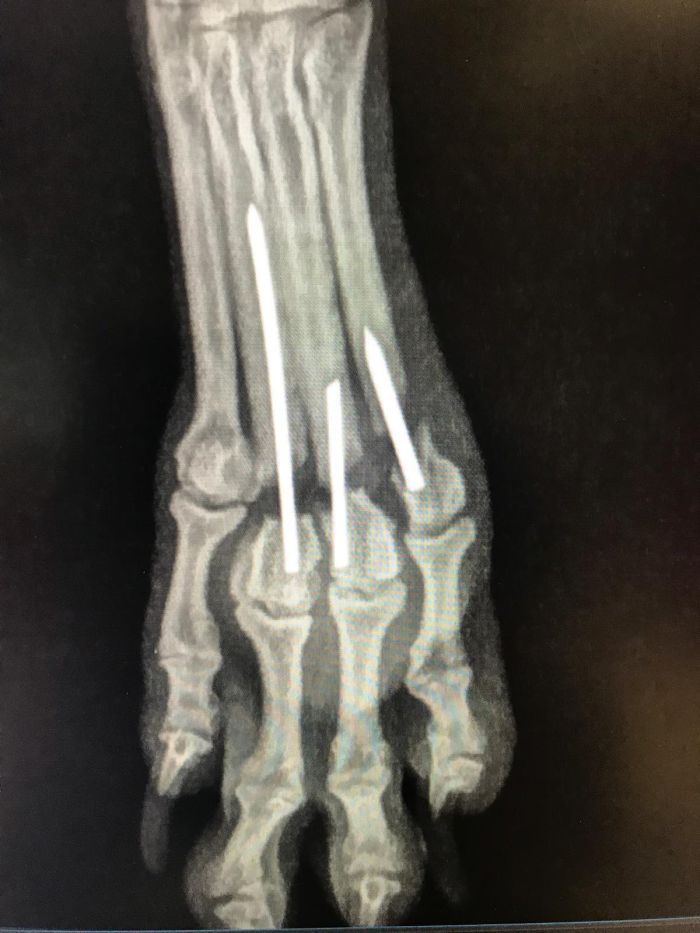

Fixation durch Markraumnägel / Pins

Zusätzlich zur Plattenosteosynthese werden öfters sogenannte Pins oder Markraumnägel verwendet, um einen Bruch in der Längsachse zu stellen.

Fall 1